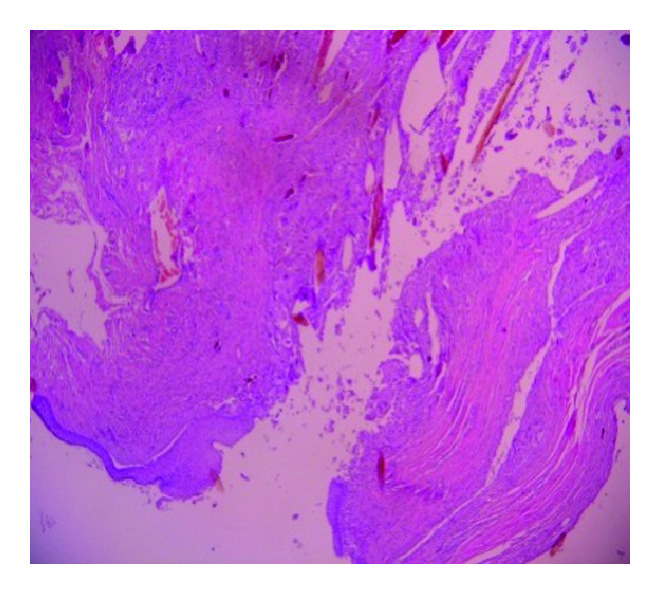

It was identified as a pilonidal sinus according to the pathology report findings of a free hair shaft into the dermis and foreign body type of intense inflammatory reaction (Figure 3). There was no recurrence for 2 years of follow-up after treatment.